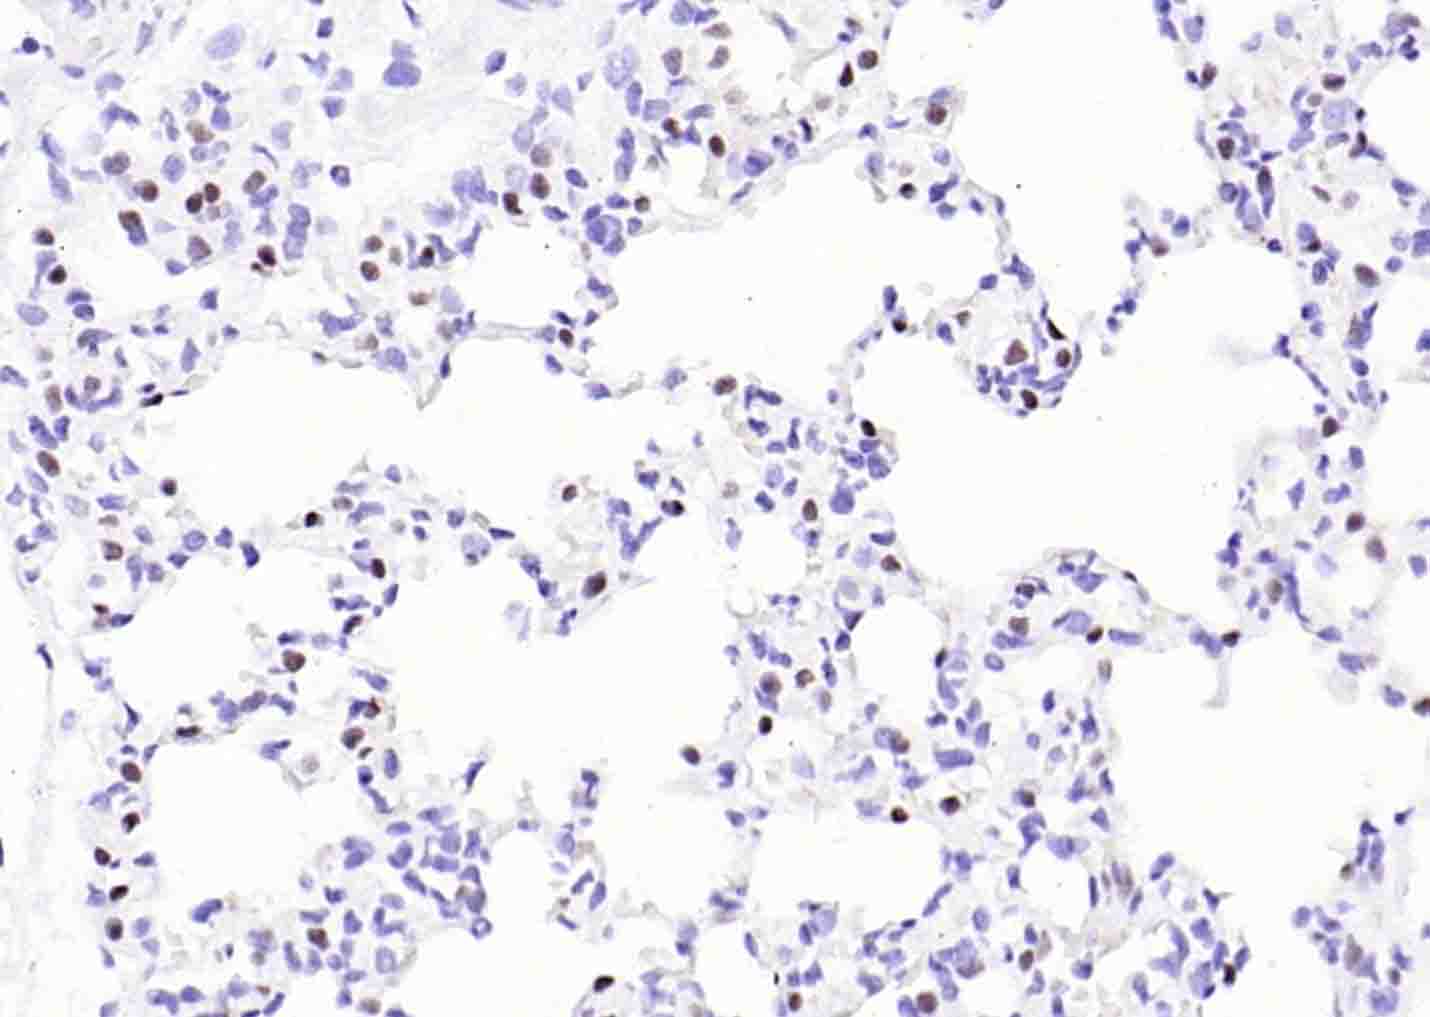

Paraformaldehyde-fixed, paraffin embedded (human lung carcinoma); Antigen retrieval by boiling in sodium citrate buffer (pH6.0) for 15min; Block endogenous peroxidase by 3% hydrogen peroxide for 20 minutes; Blocking buffer (normal goat serum) at 37°C for 30min; Incubation with (TTF1/NKX2-1 ) Monoclonal Antibody, Unconjugated (bsm-34158M) at 1:200 overnight at 4°C, followed by operating according to SP Kit(Mouse)(sp-0024) instructionsand DAB staining.